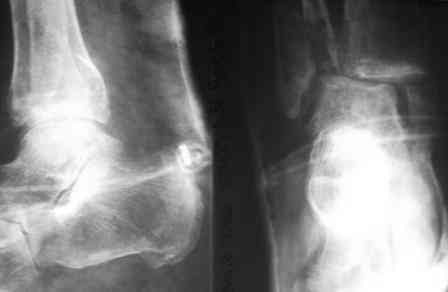

Анамнез: в 1992 г. оперирован в РНЦ «ВТО» по поводу ложного сустава шейки правого бедра (Р-снимок в приложении), 1994 перенес инсульт с исходом в правосторонний гемипарез. Передвигался без костылей, имея укорочение этой конечности на 3,5 см, порочную сгибательно-приводящую установку правого бедра и ДОА правого коленного сустава III ст. с перегрузкой латерального компартмента. Имеются дегенеративно-дистрофические изменения в поясничном отделе позвоночника. Больной до последнего времени «таксовал» на своей машине. 23 дня назад, поскользнувшись, упал в своей квартире, получил 2-х лодыжечном переломе костей правой голени с подвывихом стопы кнаружи (Р-граммы правового коленного и г/стопного суставов прилагаются). Помощь оказана в городском травмпункте г.Темиртау (Казахстан) Лечился гипсовой шиной, как рассказывает больной манипуляций на г/стопном суставе не проводили, посчитали, что все в порядке. Мое мнение - для создания опорной конечности необходимо произвести первичный артродез.Попов Виктор, г.Караганда.